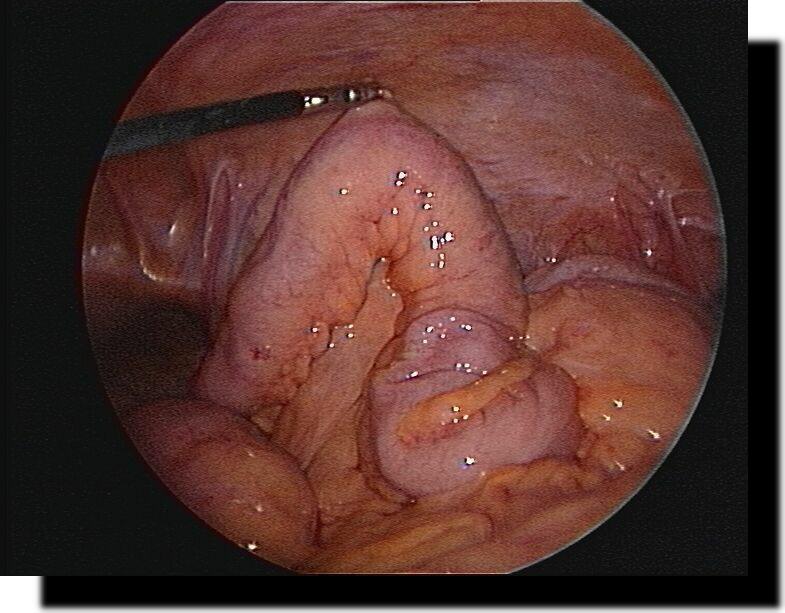

große Hiatushernie + upside-down-stomach

grosse Hiatushernie

+ upside-down-stomach